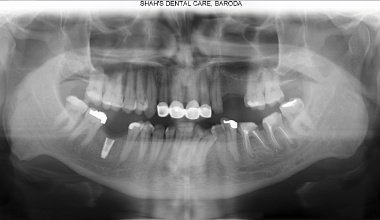

Before

Awesome Image

After